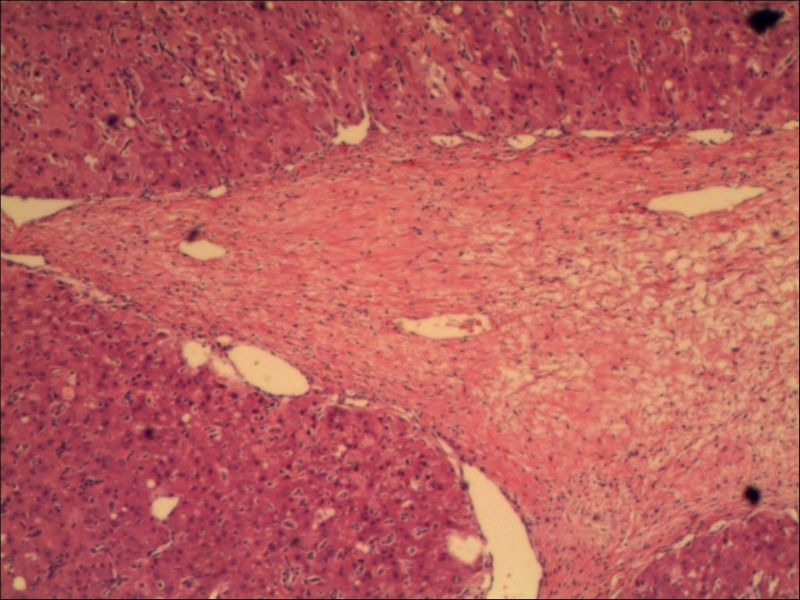

女,27岁,送检右侧卵巢肿物(另外还送检左侧卵巢肿物,大体及镜下显示为畸胎瘤),卵圆形,大小2×1×1cm,似有包膜。